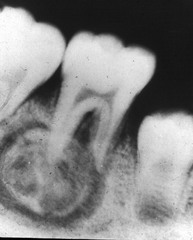

radicular cyst

-asymptomatic radiolucency associated with the root of a NONVITAL tooth